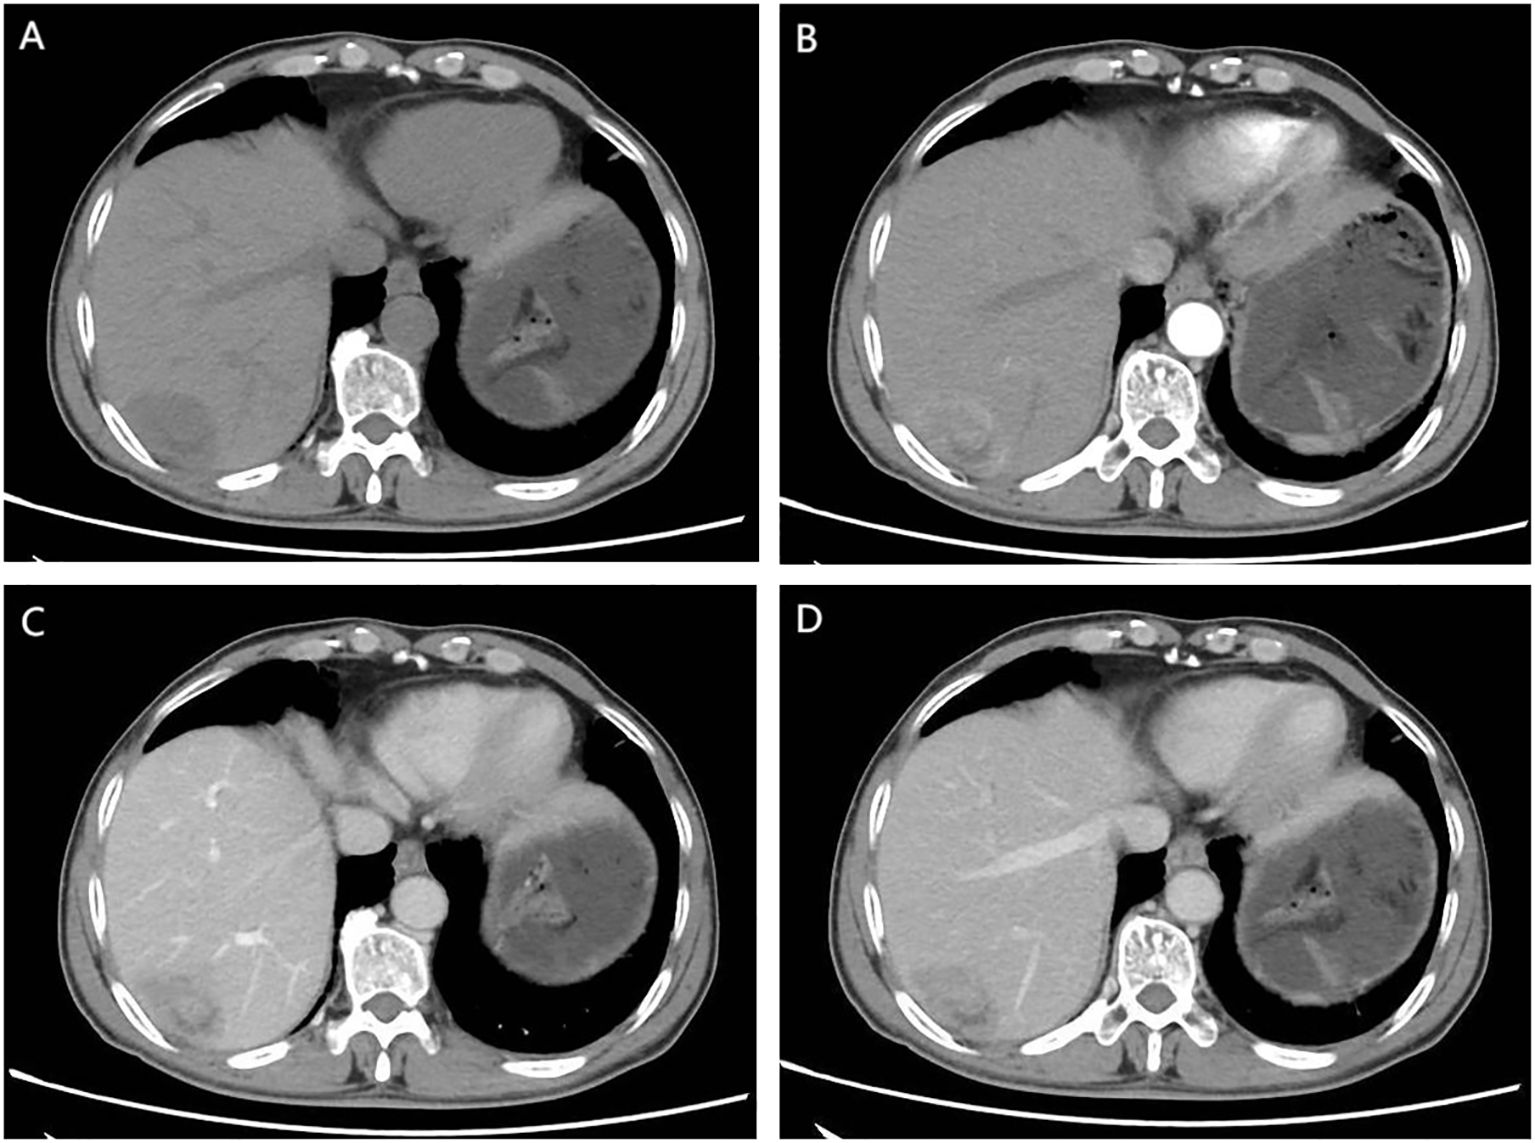

Figure 3

Figure 3. (A) (1.5 months post-operation) shows significant enlargement of SMLNs; (B, C) (2/4 months after Lenvatinib initiation) demonstrate treatment response; (D) (1-month post-Lenvatinib discontinuation) reveals significant re-enlargement SMLNs.

Given the patient’s high-risk factors for recurrence, prophylactic transarterial chemoembolization (TACE) was recommended to be performed approximately one month postoperatively after physical recovery. However, this recommendation was extrapolated from treatment guidelines established for conventional HCC rather than evidence specific to SHC (4, 5). The patient subsequently returned to the outpatient clinic 40 days after discharge, for re-examination. Imaging revealed progressive enlargement of SMLNs compared to preoperative findings, raising suspicion of lymph node metastasis (Figure 3A). Due to the presence of high recurrence risk and enlarged mesenteric lymph nodes, coupled with the absence of definitive treatment guidelines, a multidisciplinary team discussion was conducted. After thorough communication with the patient, the original prophylactic TACE regimen was maintained, with the addition of targeted therapy. The patient underwent prophylactic TACE and initiated oral lenvatinib mesilate (8mg once daily) upon hepatic function recovery. Regular outpatient follow-ups with tri-monthly imaging surveillance were arranged. Subsequent follow-ups demonstrated no new lesions. Notably, the mesenteric lymph nodes showed initial size reduction at the first re-evaluation and remained stable thereafter (Figure 3B, C). After six months of disease stability without conclusive radiological evidence of metastasis, lenvatinib was discontinued, while outpatient monitoring continued.

A repeat contrast-enhanced CT scan performed one-month after discontinuation of lenvatinib revealed no new lesions elsewhere but demonstrated significant re-enlargement of mesenteric lymph nodes. Combined with clinical history, this confirmed lymph node metastasis (Figure 3D). Combination targeted-immunotherapy (TKI and anti-PD-1 antibodies) was advised. The patient initiated the first cycle (Bevacizumab 750mg IV + Sintilimab 200mg IV administered in 21-day cycles) one month after follow-up. However, after two cycles, treatment was subsequently self-discontinued due to financial constraints, though outpatient surveillance continues without further pharmacological intervention.